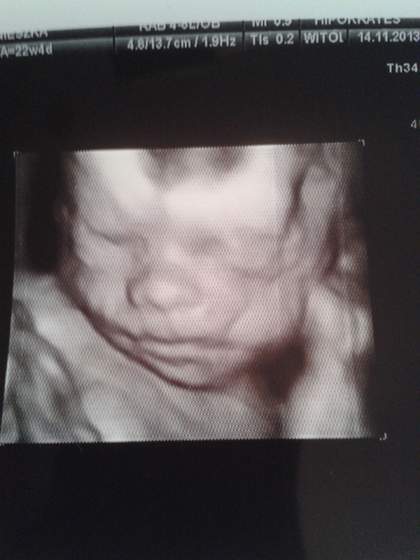

jak ja widze wszystkie przyczepy mięśniowe i nerwowe to chce mi się płakać..jeszcze to na twarzy trzeba normalnej odszukać..